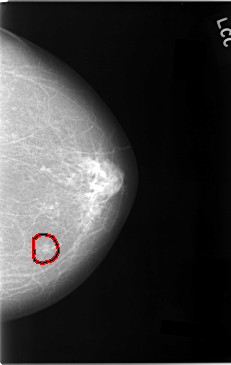

C_0027_1.LEFT_MLO

LEFT_MLO LINES 5824 PIXELS_PER_LINE 3656 BITS_PER_PIXEL 12 RESOLUTION 50 OVERLAY

FILE: C_0027_1.LEFT_MLO.OVERLAY

TOTAL_ABNORMALITIES 1

ABNORMALITY 1

LESION_TYPE MASS SHAPE OVAL MARGINS ILL_DEFINED

ASSESSMENT 5

SUBTLETY 2

PATHOLOGY MALIGNANT

TOTAL_OUTLINES 1

BOUNDARY